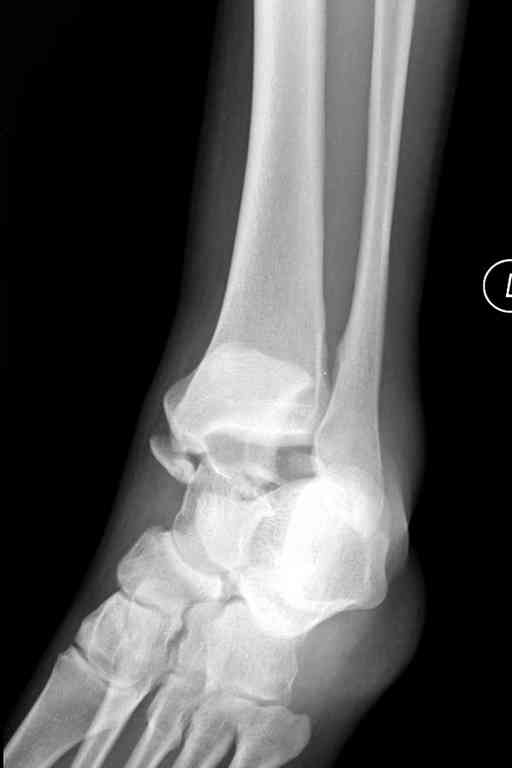

Переломовывих тарана с повреждением медиальной стороны. Через 4 часа после поступления проведена репозиция и фиксация тарана после Irrigation&Debridment. Частичное несращение медиальной лодыжки не беспокоит, вернулся к активному образу жизни. Полная нагрузка разрешена через 11 недель. Финальные снимки через 11 месяцев.

переднезаднего снимка, так что через какую лодыжку идти не могу сказать.